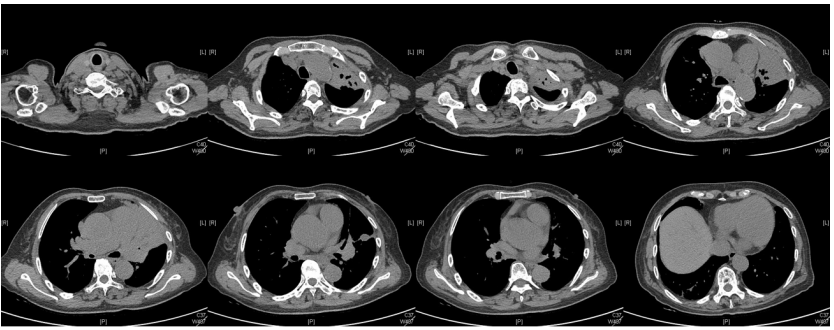

由于厌氧菌培养非常困难,既往我们对厌氧菌的认知仅限于在消化道定植,对其致病机制以及何种情况下致病并不非常清楚。厌氧菌定植于皮肤黏膜,是一种内源性微生物,感染发生率高,可导致严重、致死性感染。由于标本采集和转运的特殊性,使厌氧菌难以分离;加之其培养困难,体外生长慢,所以既往很难识别。厌氧菌在治疗方面存在一定挑战,如往往混合多重感染,且易产生耐药,也会因治疗延迟导致治疗失败。随着近10年来NGS技术的应用和普及,我们对厌氧菌的认识得以提升。常见的致病厌氧菌分为革兰阳性球菌、革兰阴性球菌、革兰阳性非芽孢杆菌、革兰阳性芽孢杆菌以及革兰阴性杆菌(表1)。革兰阳性非芽孢杆菌中可能致病的是放线菌,例如龋齿放线菌参与龋齿的发病过程。革兰阳性芽孢杆菌往往具有致病性,其中产气荚膜杆菌、艰难梭菌/难辨梭状芽孢杆菌、肉毒杆菌/肉毒梭菌、破伤风梭菌/杆菌具有强致病性。革兰阴性杆菌中的拟杆菌属对青霉素类药物具有很强的耐药性,易致青霉素治疗失败。临床中我们与厌氧菌的接触逐渐增多,对其特点也会愈发熟悉,对于临床诊断和治疗也会有所帮助。在NGS报告中通常会将检出的厌氧菌列为“C类”,定义为致病性C类—呼吸道正常微生态菌群,一般不导致感染。但当患者存在误吸风险时,需关注厌氧菌引起肺脓肿的可能。此时就需要针对患者的危险因素、临床表现、影像学、病原学以及气管镜下特点等进行综合分析。微小单胞菌最早是通过培养进行鉴定。瑞士2015—2022年132例病例报告的培养鉴定结果显示,血液中检出微小单胞菌37例(28%),肺内(肺脓肿、脓胸)检出29例(22%),总体病死率较低(5.3%)。国内周华教授团队开展的一项回顾性研究分析了2019年1月至2020年7月经病理活检和mNGS诊断的5例与微小单胞菌相关的慢性肺脓肿患者。患者的平均病程为6.5个月,共同特征是口腔卫生差,有酗酒史,且CT表现为边界不规则的高密度团块状实变影,并且在病灶中间可见液化性坏死,但没有发现气液平面或空腔,所以前期易被误诊为肺癌。下图1是该研究报告中病例3的肺部CT表现。时间点1:首次就诊时,左下叶可见团块状肺不张,伴周围磨玻璃样渗出病变,中心坏死不明显,可见细小空气囊泡影。时间点2:发病8个月时,可见大面积肺实变,增强CT示病灶内有液化坏死和小空洞。时间点3:经过3个月的有效抗厌氧菌治疗,病灶明显缩小,遗留空洞和纤维增殖病灶。图2是病例4的肺部CT表现。时间点1:患者首次就诊时,右上叶可见肿块样肺部实变影。时间点2:发病8个月时增强CT,可见实变明显增大,病灶内出现液化坏死。时间点3:经过3个月的有效治疗,病灶明显缩小,有残留空洞和纤维瘢痕样病变。由于通过影像学鉴别该病与肺癌具有挑战性,所以5例患者都接受了支气管镜检查和CT引导下经皮肺活检。5例患者经组织活检或支气管肺泡灌洗液(BALF)标本mNGS检测到微小单胞菌。病例: 女性, 67岁, 主诉"咳嗽咳痰2个月"。现病史:2个月前,患者家属感染新冠病毒(家属新冠抗原阳性)之后,患者出现咳嗽咳黄脓痰,无痰中带血及痰液拉丝,痰无臭味,无胸闷气短及胸痛,无咽痛咽痒,无鼻塞流涕。6月9日于当地市医院住院,住院期间出现发热,体温最高38.6℃,无寒战,查新冠病毒核酸阳性,予先诺特韦/利托那韦片口服治疗。查胸部CT见左肺上叶软组织影,左肺上叶炎症。诊断肺脓肿,予头孢唑肟联合莫西沙星,治疗后复查胸部CT(6月26日)病灶较6月9日明显吸收好转。6月14日气管镜检査见左肺上叶支气管开口狭窄,见大量脓性痰液堵塞支气管开口(病原学结果家属无法提供)。6月30日办理出院后仍有咳黄脓痰,无发热畏寒,口服止咳化痰药物,未使用抗生素。7月30日复诊胸部CT见左肺上叶异常密度较前增大。8月2日再次于当地市人民医院住院。8月4日气管镜检查: 左肺上叶黏膜肿胀肥厚, 管腔狭窄, 见大量白色干酪样分泌物涌出, 支气管镜不能进入。内科予莫西沙星静滴治疗10天, 外科予莫西沙星联合哌拉西林他唑巴坦静滴9天。复查胸部CT见病灶较前进展, 且右肺出现新发感染病灶。病程中患者饮食可, 睡眠差, 二便正常, 体重减轻5 kg。既往对阿莫西林过敏, 表现为口服阿莫西林后全身皮疹。否认嗜酒史及吸烟史。入院后胸部增强CT可见病灶内液化坏死,同时伴有小的空气囊泡影(图3)。患者有胸痛症状。气管镜检查发现气道内有痰栓或黏液栓阻塞征象(图4)。灌洗液tNGS结果回示:微小单胞菌(序列数2762),巨细胞病毒(序列数171),副流感病毒(序列数79),EB病毒(序列数61)。考虑病毒不会导致气道内如此改变,但由于微小单胞菌属于常见口腔定植菌,此时也不能完全确定微小单胞菌是否为引起感染的主要责任病原体。8月24日起予莫西沙星0.4 g qd ivgtt+哌拉西林他唑巴坦4.5 g q8h ivgtt。经过上述治疗,患者局部病灶有所吸收,但整个肺叶并无明显改善(图5)。气管镜检查仍然发现气道内有较黏稠的黏液栓阻塞气道开口(图6)。治疗经过:气管镜下予以局部冲洗,再次送检tNGS。9月7日结果回示:微小单胞菌(序列数6464),较前明显增多;副流感病毒(序列数998),EB病毒(序列数331)。9月9日起调整治疗方案为美罗培南1 g q8h。9月12日复查患者胸部CT,可见肺通气部分改善,肺组织内实变较前吸收(图7)。第三次气管镜检查仍可见少量痰栓嵌塞在远端支气管开口(图8)。患者此后转入医联体医院继续抗感染治疗。病例2:女性,54岁。主诉:咳嗽咳痰2个月,发热1周。现病史:入院2个月前,患者在西南地区旅游时感冒,出现咳嗽咳痰,白痰为主,量多,无胸痛,无发热,无痰中带血,咳时气短。于河北某诊所间断输液治疗14天(具体不详),期间口服中药治疗,症状未缓解。入院3周前(2023-09-07)就诊于当地县医院,查胸部CT提示右肺炎症,静脉滴注氨曲南、左氧氟沙星、氨溴索治疗1周,症状未缓解。2023年9月14日复查胸部CT显示右肺炎症较前加重,于当地中心医院住院。动脉血气分析:pH 7.43,PaCO2 38.4 mmHg,PaO2 67 mmHg,SaO2 94.2%;血沉90 mm/h;生化:白蛋白35.3 g/L;CRP 82.7 mg/L;血常规:WBC 9.75×109/L,NEU 6.83×109/L,HGB 104 g/L。静脉滴注莫西沙星。入院10天前,行肺穿刺活检,病理回报为少量肺组织及纤维结缔组织,炭末沉积,较多中性白粒细胞、淋巴细胞及浆细胞浸润,伴脓肿形成;肺穿刺mNGS结果回报:微小单孢菌(序列数2650),鲍曼不动杆菌(序列数17),人类疱疹病毒4型(序列数60),人类疱疹病毒7型(序列数5),文氏密螺旋体(序列数4337),解卵磷脂密螺旋体(序列数1121),齿垢密螺旋体(序列数698)。调整抗生素为头孢哌酮舒巴坦2 g q12h。入院1周前,出现发热,体温最高38.5℃,不伴寒战,咳嗽咳痰无加重,无咯血;复查血常规、PCT、CRP均明显增高(未见报告单);复查胸部X线提示右肺炎症范围增大,右侧胸腔积液。更换抗生素为哌拉西林他唑巴坦4.5 g q8h。4天前,支气管镜下见右肺下叶背段支气管略狭窄,黏膜水肿,可见脓性分泌物溢出。BALF革兰染色查见革兰阴性杆菌,抗酸染色、霉菌未见异常,培养未回报。患者体温逐渐降至正常,咳嗽咳痰有所减轻,复查胸部CT提示右肺高密度影,右侧胸腔积液较前增多。为求进一步诊治来我院就诊被收入院。既往甲状腺功能减退病史5年,目前口服优甲乐治疗,监测甲状腺功能指标在正常范围。20年前因宫外孕行手术治疗。2023年10月8日胸部CT示胸膜下斑片状坏死,纵隔窗可见微小空气囊泡影及密度不均匀液化坏死(图9)。治疗:9月28日至10月13日莫西沙星0.4 g qd ivgtt+哌拉西林他唑巴坦钠4.5 g q8h ivgtt。最终患者病灶吸收好转并顺利出院。患者男性,42岁。主因间断咳嗽、咳痰1月余,左侧胸痛、气短2天入院。现病史:入院前1月余(2022-07-19),患者无明显诱因出现咳嗽,咳白痰,痰中有少量鲜红色血丝,左侧胸痛(为钝痛),深吸气后加重,就诊于当地医院。完善肺动脉CTPA:示左上肺动脉舌段分支局部管腔可见线条样低密度充盈缺损,考虑肺栓塞;左肺上叶实性病变伴不均匀强化,性质待定,部分为肺梗死改变可能,纵隔多发稍大淋巴结,性质待定;右肺下叶后基底段可见一不规则实性结节,边缘可见多发毛刺,直径约0.7 cm。当地医院考虑肺栓塞不除外,肺部感染?右肺下叶结节,予莫西沙星抗感染,低分子肝素抗凝,乙酰半胱氨酸化痰。完善CT引导下肺穿刺活检,病理示:肺泡腔扩张伴上皮轻度增生,肺泡间隔纤维组织增生伴散在炎细胞浸润,未见恶性病变。院外规律应用甲磺酸艾多沙班60 mg bid抗凝,先后间断应用左氧氟沙星0.5 g qd、头孢类抗生素(具体药物、剂量不详)抗感染。患者仍有间渐咳黄白痰,量不多,痰中有少量鲜红色血丝;无畏寒、发热、胸痛、夜间阵发性呼吸困难症状,无尿少、双下肢水肿,无口干、咽干,无牙齿成片脱落,无晨僵、关节肿痛,周身无皮疹,无盗汗乏力。2天前(2022-09-16)患者无明显诱因再次出现左侧胸痛,疼痛剧烈,深吸气、咳嗽及改变体位时加重,伴气短,就诊于我院急诊。完善肺动脉CTPA:肺动脉主干及其各叶段分支未见明显充盈缺损,左肺上叶舌段团块影,最大截面约7.6 cm×5.3 cm,边界不清,周围可见晕征;增强扫描不均匀强化,邻近胸膜增厚,性质待定,建议穿刺活检;纵隔及左肺门多发淋巴结显影。血细胞分析:WBC 11.09×109/L,NEU% 80.8%,NEU 8.95×109/L;CRP 54 mg/L,PCT 0.07 ng/ml。患者自发病以来,精神状、食欲及睡眠均一般,大小便正常,体重下降5 kg。2022年9月14日外院胸部增强CT:胸膜下楔形的影像学表现可见少量小气泡囊以及液化坏死病灶(图10)。初始考虑肺部肿瘤及肺栓塞。经过初步抗感染及抗凝治疗,患者病情无缓解,2022年9月27日患者突发胸痛,下肺影像加重并且出现脓胸(图11)。行胸腔穿刺并将脓液送检mNGS,结果回报:牙龈卟啉单胞菌(序列数3)。尽管序列数很低,但考虑是脓肿穿刺结果,因此考虑该菌致病可能。抗厌氧菌治疗:9月16-28日莫西沙星0.4 g qd ivgtt,9月23日-10月12日美罗培南1 g q12h ivgtt,9月28日-10月8日万古霉素1 g q12h ivgtt,10月13-18日莫西沙星0.4 g qd ivgtt+甲硝唑0.5 g tid ivgtt。患者肺脓肿的整体治疗时间约为3个月,病灶逐渐吸收,最终形成一些纤维索条影(图12,图13)。1年后复查病灶基本吸收(图14)。图14 1年后复查胸部CT(2023-08-08)微小单胞菌和卟啉单胞菌这两种厌氧菌在临床中需要引起重视,它们容易引起肺脓肿/脓胸。2024年国内学者Li Yao等在Diagn Microbiol Infect Dis 杂志发表了一篇牙髓卟啉单胞菌感染所致肺脓肿的病例报告,文章也提到在胸水或肺组织活检中,通过mNGS同时检出了微小单胞菌和卟啉单胞菌感染引起的肺脓肿。文章还回顾总结了既往发表的厌氧菌感染引起肺脓肿的病例,2010年报道的是1例脑脓肿患者,2019年报道1例脑炎患者,2022年报道1例脓胸伴呼吸衰竭患者。3例患者预后都比较好,可见厌氧菌亦可导致肺外多部位感染。对于厌氧菌所致肺脓肿的诊断及其引起的脓胸,目前的文献报道仍然较少,我们对它们的认知也有限,因此也提醒大家关注相关疾病的诊断和治疗。我们也已将本研究小组8例微小单胞菌所致肺脓肿的系列病例的研究结果发表(Front Cell Infect Microbiol, 2024, 14: 1416884),可供需要的同行参考。对于厌氧菌感染,我们需要提高警惕。厌氧菌往往在口咽部定植,其引起的脓肿/感染往往多为亚急性或慢性起病。患者通常有发热、胸痛症状,脓肿会逐渐进展。由于厌氧菌与人体本身是一种长期共生的关系,人体对厌氧菌的免疫识别可能处于较低的防御反应状态,所以会形成一个亚急性或慢性的发病过程。通常情况下,因厌氧菌的菌群发生了移位,从卫生条件不好的口腔扩展到相对无菌的肺内,同时开始增殖,由此可能导致感染。因此,对于酗酒以及口腔卫生非常差的人群,我们要重视对其风险因素和病史的排查。患者就诊时可能病情并不重,有胸痛或咯血,很容易误诊为肺部肿瘤,往往在这种情况下进行肺穿刺或气管镜检查,mNGS可以发现较大序列数的厌氧菌。但在mNGS检出厌氧菌后的诊断过程中又容易形成误判——究竟是致病菌,还是定植菌?此时结合患者其他病史和影像学特点(有脓肿/痰栓形成,微小空气气囊泡影),可能提示厌氧菌感染。然而,厌氧菌感染在病原学和影像学诊断方面仍然存在诸多困难,极易漏诊和误诊。微小单胞菌感染患者在气管镜下可以看到典型的脓性分泌物嵌塞气道,导致气道阻塞,也会造成远端气道和肺泡引流障碍。所以,及时处理气道内痰栓,改善引流,可能是使患者获得良好预后的关键。厌氧菌肺脓肿的吸收比较缓慢,抗感染的疗程也比较长,需要在后期诊疗过程中密切随访和观察患者对治疗的反应以及耐药等问题,及时调整治疗方案,适当延长疗程。